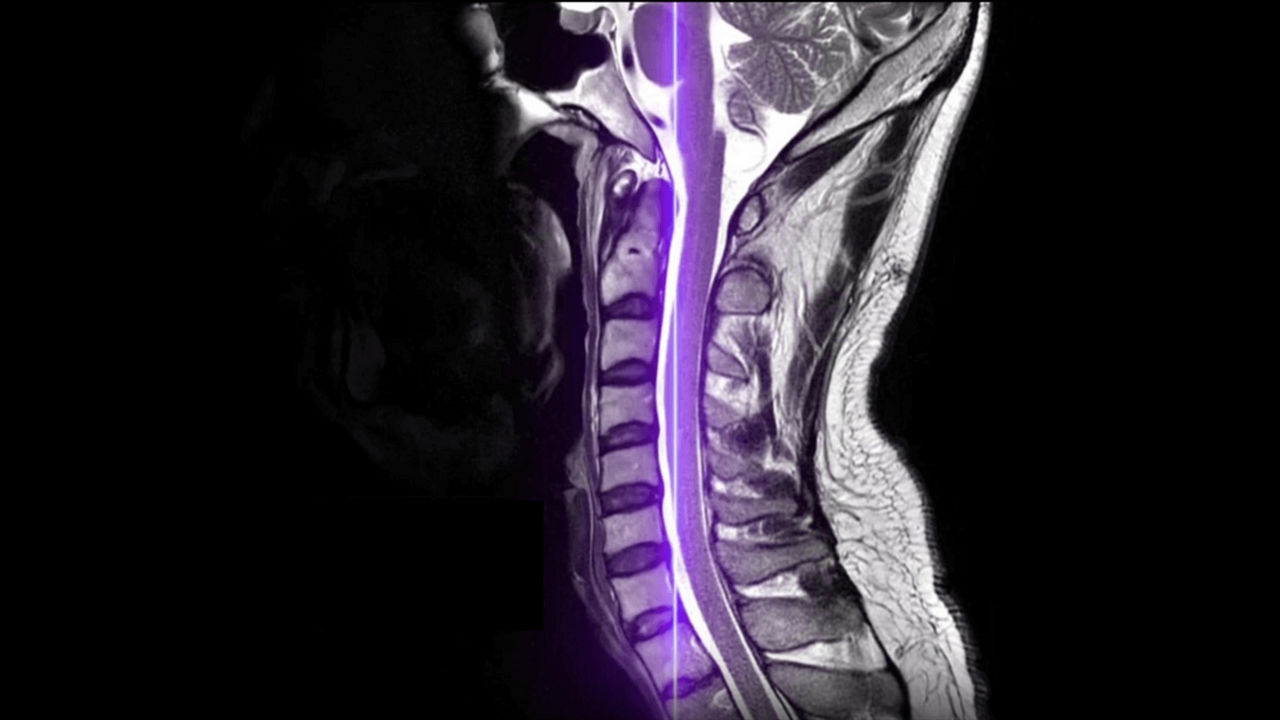

Meet our next-generation SIGNA MRI scanners & solutions

SIGNA MRI Scanners

Our 1.5T, 3T, PET/MR and 7T scanners deliver the latest in imaging innovation with AIR Recon DL, and AIR Coils.